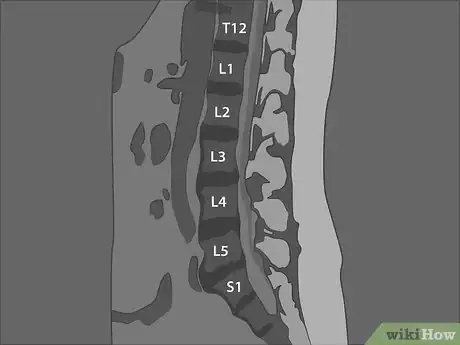

1Count the vertebrae of your lumbar spine. The vertebrae in your spine are divided into 5 regions. The lumbar region, consisting of 5 vertebrae, is the lowest region of your spine with movable vertebrae. In the 2 lower regions, the sacrum and the coccyx, the vertebrae are fused together.[6]

- The 5 vertebrae of your lumbar spine are numbered from 1 to 5, starting at the top and going down. You can count them down on your sagittal MRI.

- Medically, the vertebrae are labeled with an "L" indicating the lumbar region, followed by the number. For example, the second vertebra from the top of your lumbar spine is called "L2."

Tip: A sagittal image may also show the thoracic vertebrae above the lumbar section of your spine. To correctly identify the lumbar vertebrae, it may be easier to count up from the bottom.